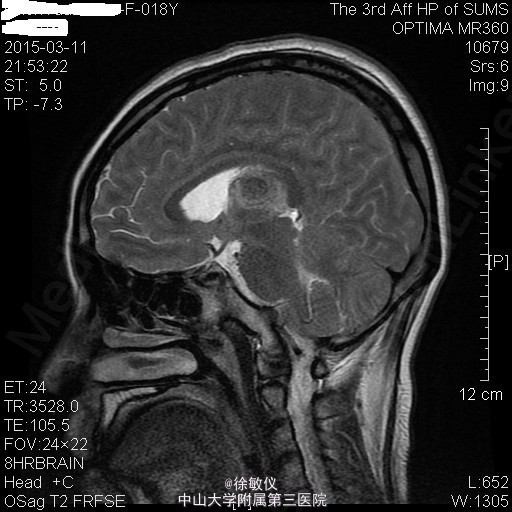

青年女性,主诉:左侧面部麻木,右侧听力下降半年。

查体:神清,查体合作,对答切题。颈软,无抵抗。左侧面部浅感觉痛觉过敏。双侧眼球运动正常,双侧视野粗测无缺损。右侧听力粗测听力下降。双侧瞳孔等大等圆,直径3mm,对光反射灵敏。双侧肢体肌力5级,肌张力正常。病理征未引出。 辅查:头颅MR提示:双侧桥小脑角区、鞍上池右侧、左侧三叉神经颅内段及枕部多发占位,考虑为神经纤维瘤病II型。

诊断:双侧听神经鞘瘤 排除手术禁忌症后,在全麻下行显微镜下经右侧乙状窦后入路右侧桥小脑角区占位病变切除术,术程顺利。术后于SICU监护治疗1天后顺利转回我科,予抗感染、脱水降颅压、营养支持及对症治疗,患者恢复良好。 术后病理诊断:(桥小脑角占位)形态结合免疫组化结果,符合神经鞘瘤。免疫组化结果(⑥):S100(+),Vim(+),Ki-67(1%+)。 术后复查头颅MR示:1、右侧听神经瘤术后改变,右侧桥小脑角区占位大部分已切除,术区少量积液同前;左侧侧脑室内少量积血,基本同前。 2、左侧桥小脑角区、鞍上池右侧、左侧三叉神经颅内段及枕部多发占位同前,考虑神经纤维瘤病。